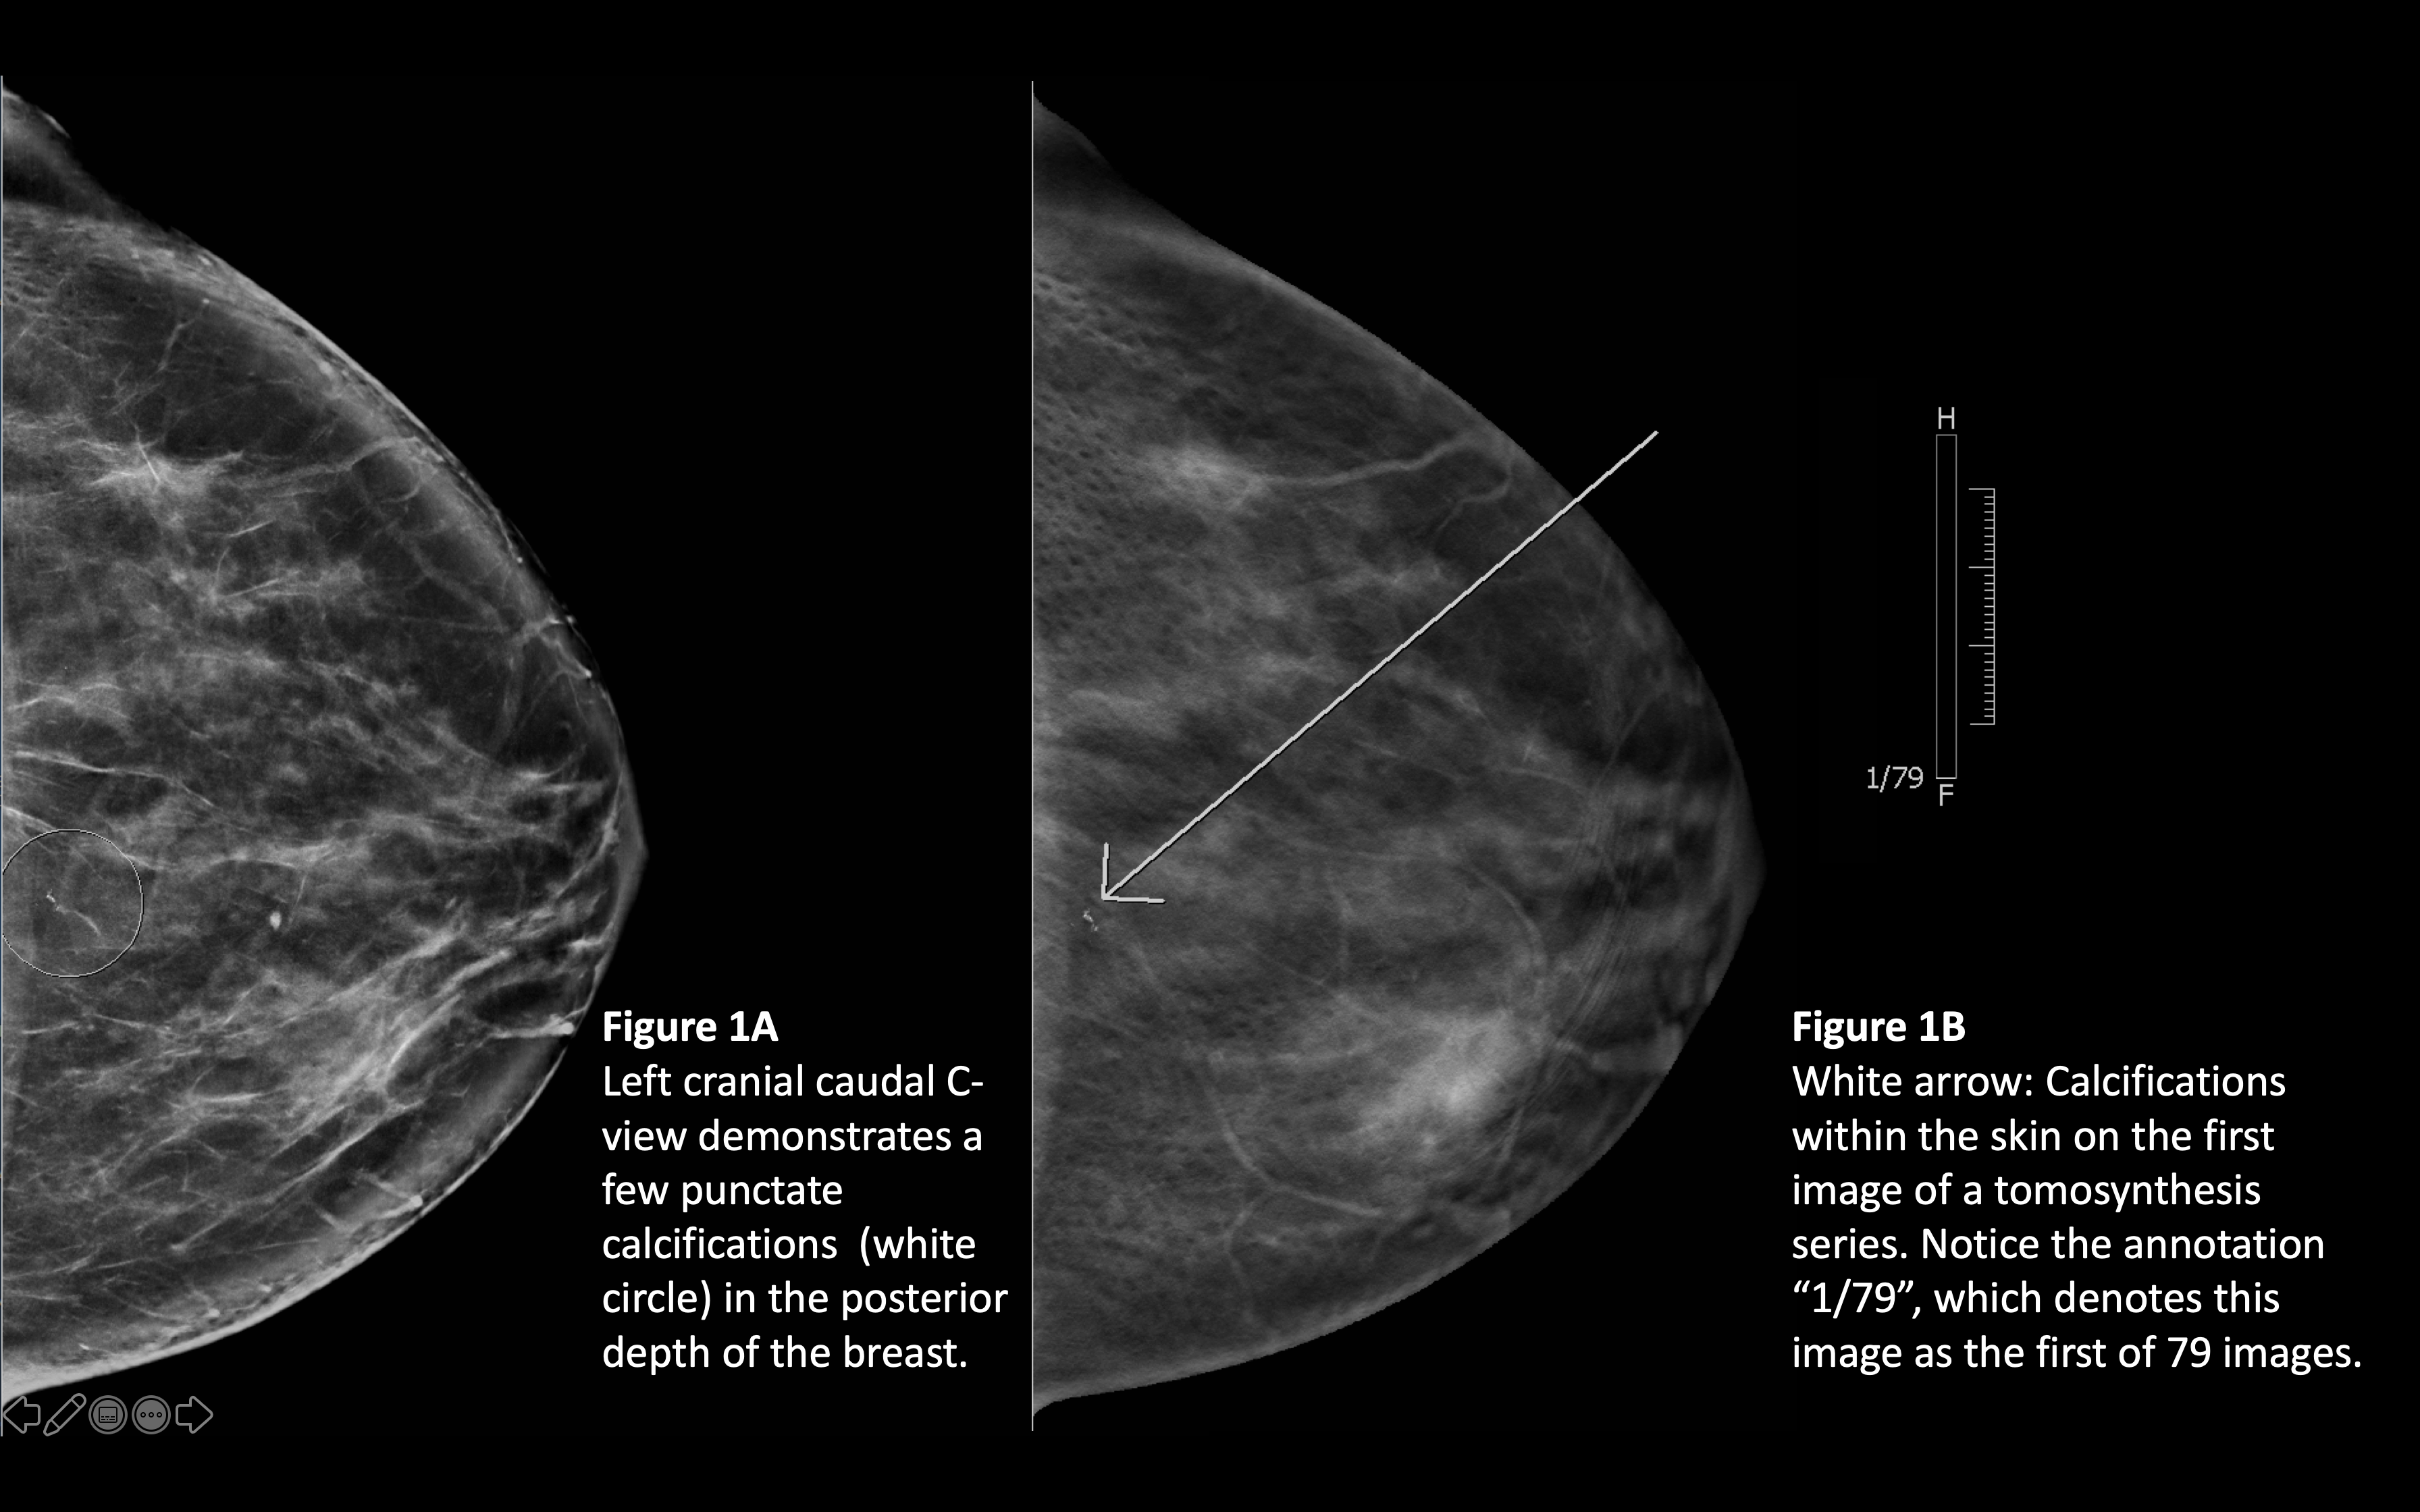

They appear as white spots or flecks on a mammogram but can't be felt during a breast exam. A new group has formed. For women treated for breast cancer in the past, calcifications may also be due.

There are numerous causes for calcium deposits in the breasts, including: But, japanese food natto has the ability to decalcify and maintain uniform level of calcium throughout the body and parts. Breast calcifications. california pacific medical center: